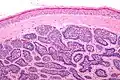

Micrograph of a dermal cylindroma in H&E stain. -

Dermal cylindromas are:

- Dermal lesions consisting of nests of cells that are surrounded by hyaline (i.e., glassy, eosinophilic, acellular) material and have:

- Hyperchromatic nuclei that may palisade (columnar nuclei arranged around the periphery of the cell nests with their short axis tangential to the nest periphery), and

- Cells with lighter staining ovoid nuclei at their centre.

They lack of a significant number of lymphocytes; this differentiates them from spiradenomas.